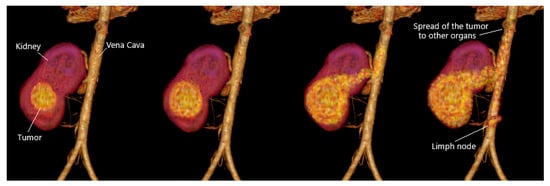

2.1.4. Kidney Tumor Stage